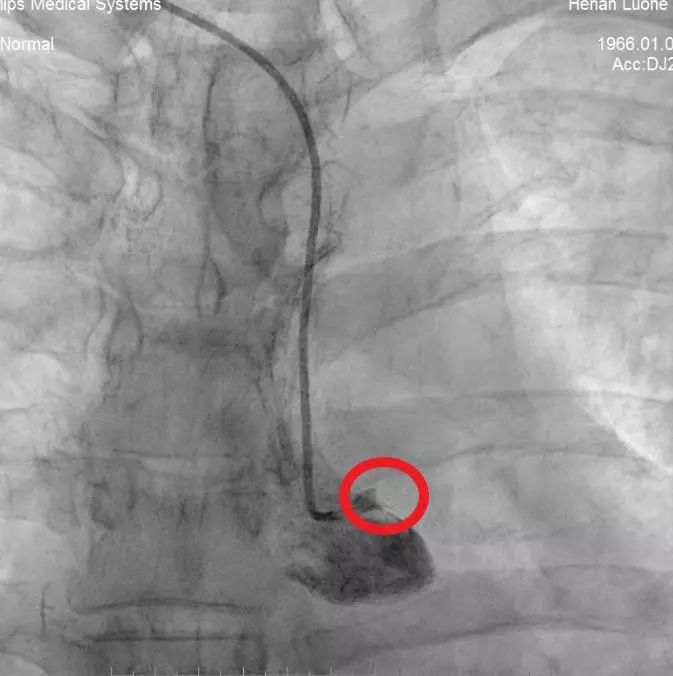

为病人安装主动脉内球囊反搏装置(IABP)

“就在手术紧要关头,监护上显示病人血压为85/50mmHg,提示病人心泵功能差,如果冒然直接开通血管,极有可能立即诱发不良事件。”心内科一病区主治医师王浩然回忆,刘东亮教授随即指示彭庚给予主动脉球囊反搏导管置入,维持血压,同时立即指引导管到位,指引导丝迅速通过闭塞病变,导丝通过后造影显示病人左主干血管内存在大块血栓,且血流不通畅。